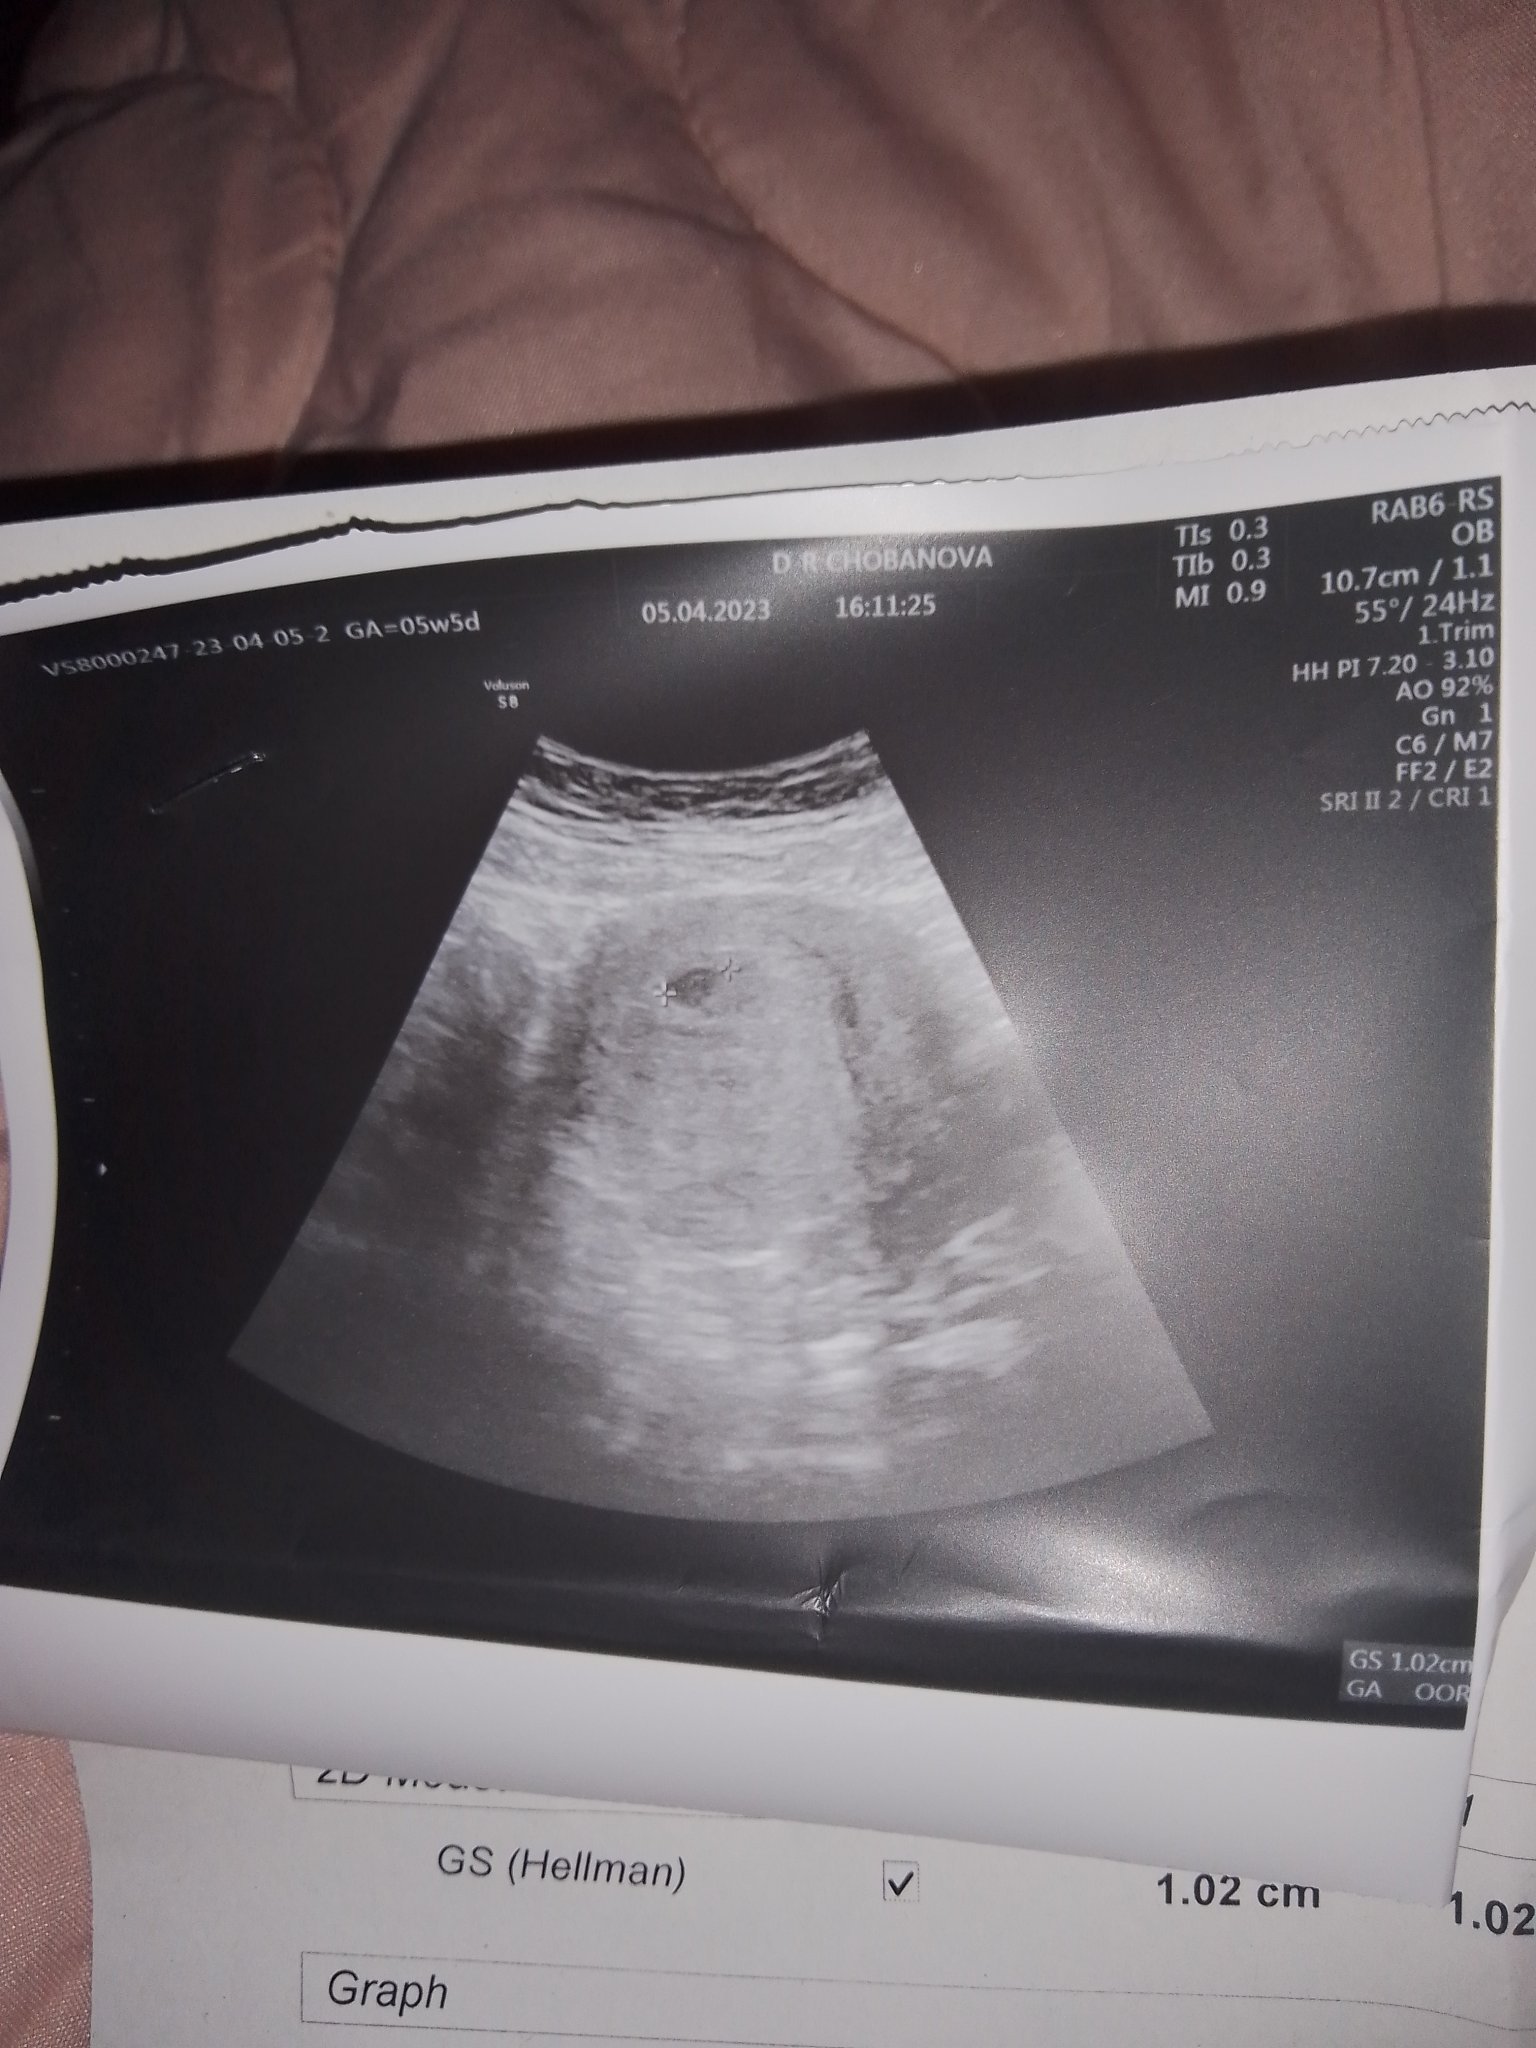

ето резултат съжалявам че качвам по късно както ви каза но като бяхме миналата сряда неможаха да го видят и ето от вчера снимчица една точица а всъщност целият ми живот......!!!!! Пожелавам на всички дами да усетят тази тръпка тази радост ♥️♥️♥️♥️♥️♥️♥️♥️♥️